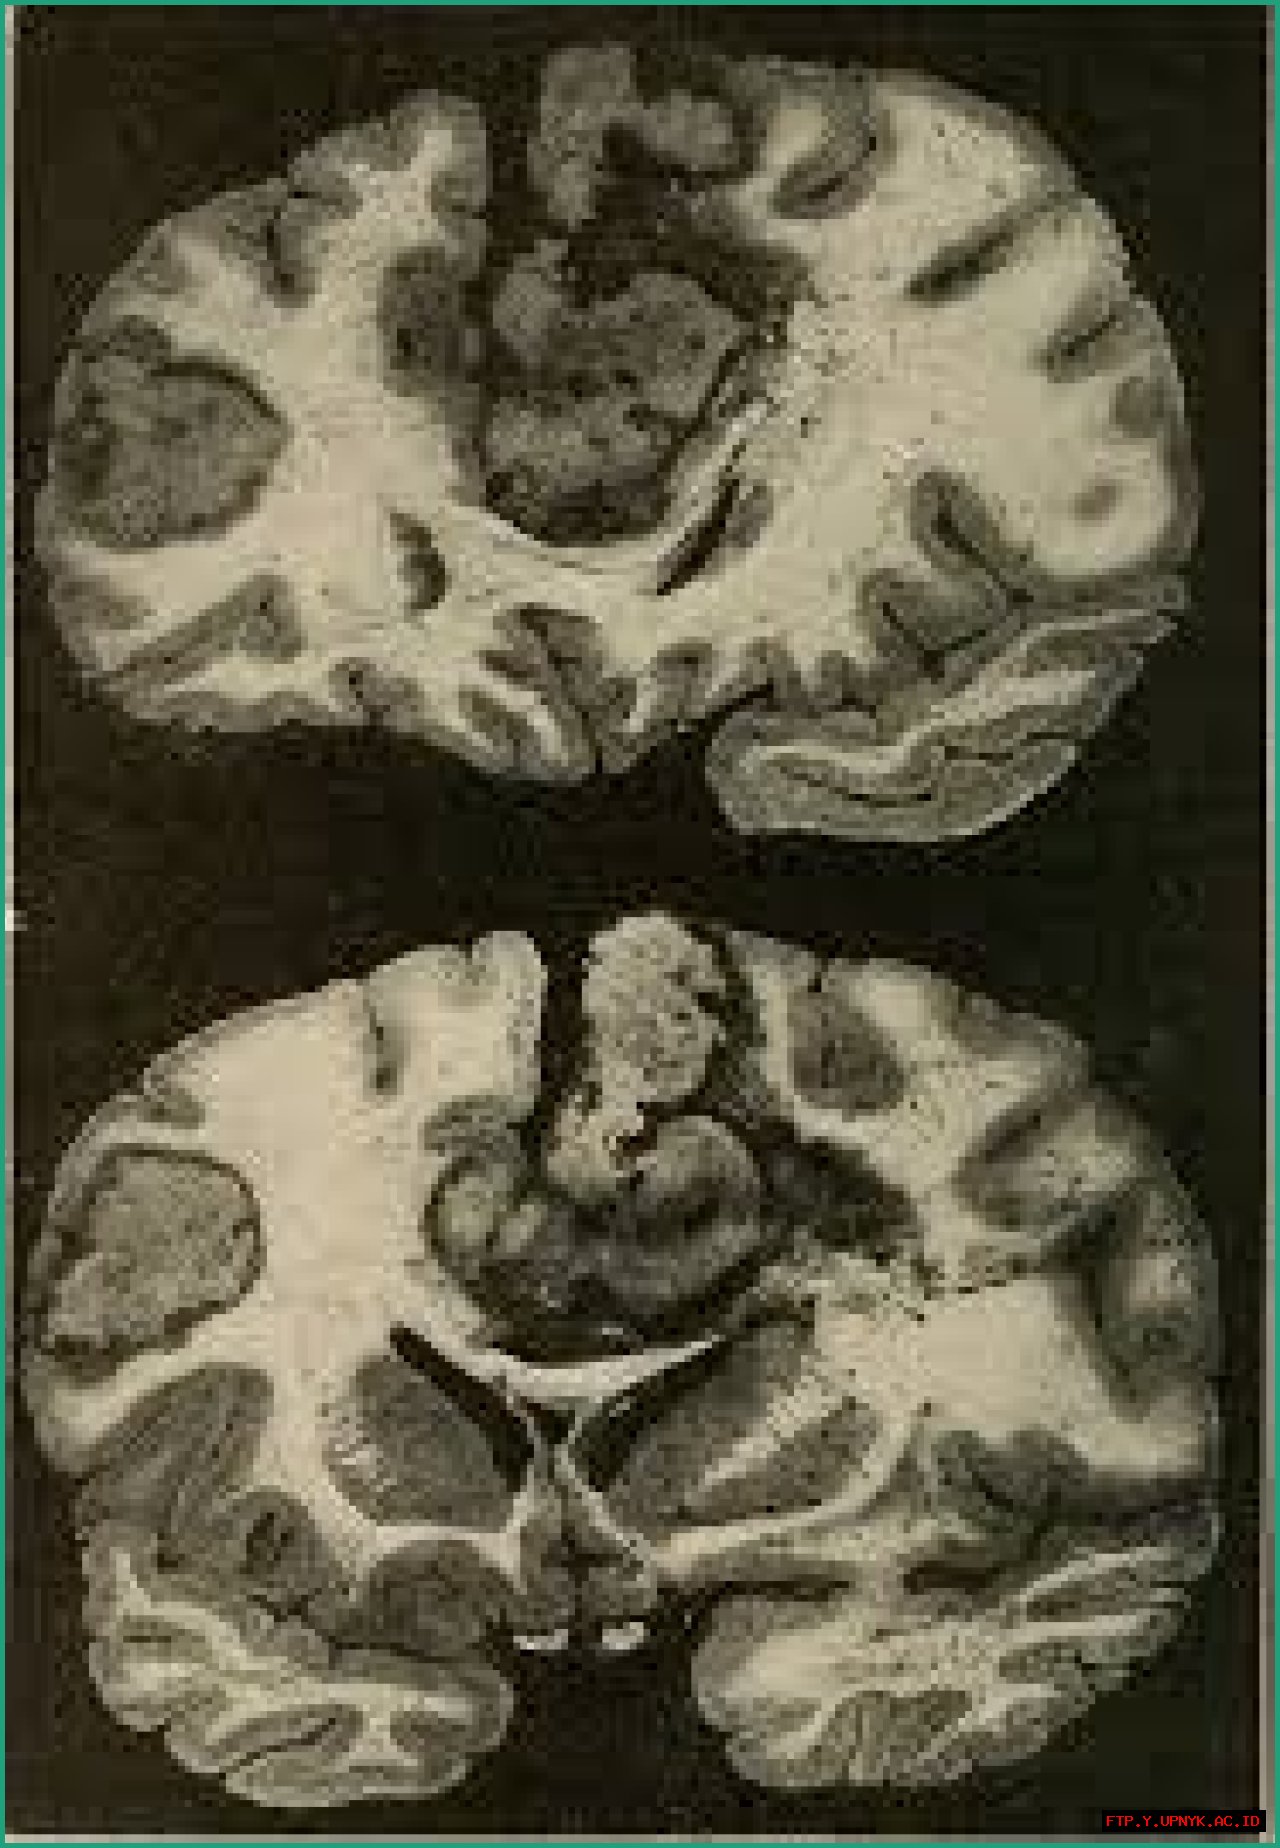

Anything alexia is caused by damage to the brain's left hemisphere, which is responsible for language processing. This damage can be caused by a stroke, a head injury, or a brain tumor. Anything alexia can also be a symptom of dementia.

• Damage to the brain's left hemisphere: The brain's left hemisphere is responsible for language processing. Damage to this area of the brain can cause anything alexia.

• Stroke: A stroke is a sudden loss of blood flow to the brain. A stroke can damage the brain's left hemisphere and cause anything alexia.

• Head injury: A head injury can damage the brain's left hemisphere and cause anything alexia.

• Brain tumor: A brain tumor can damage the brain's left hemisphere and cause anything alexia.